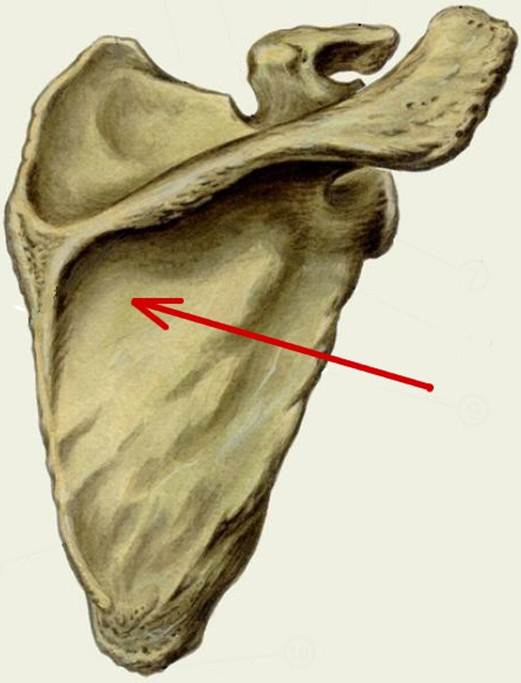

S: Стрелка указывает на fossa supraspinata

S: Стрелка указывает на fossa infraspinata

S: Стрелка указывает на angulus superior

S: Стрелка указывает на angulus inferior

S: Стрелка указывает на cavitas glenoidalis